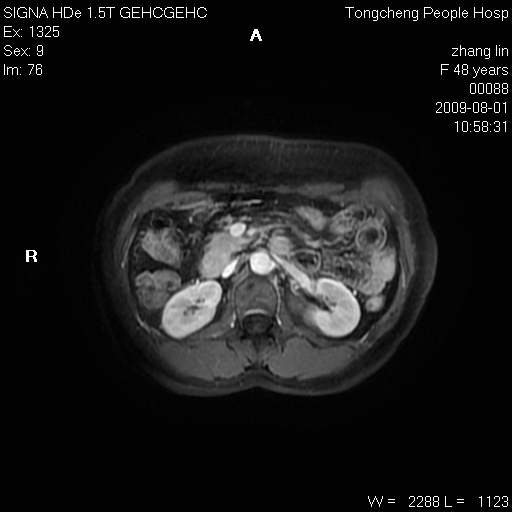

女,48岁。健康体检,彩超发现右肾占位性病变。平素健康。

临床诊断:右肾占位性病变,性质待定(囊肿?肿瘤?)。

上中腹部mr平扫+增强扫描,图像如下:

右肾上极见一类圆形病灶,t1wi呈等信号t2wi呈等高混杂信号,三期增强无强化,边界清---考虑囊肿出血。

同反相位均表现为等信号,病变无强化,考虑含蛋白的囊肿可能,弥散加权相或许有些帮助,